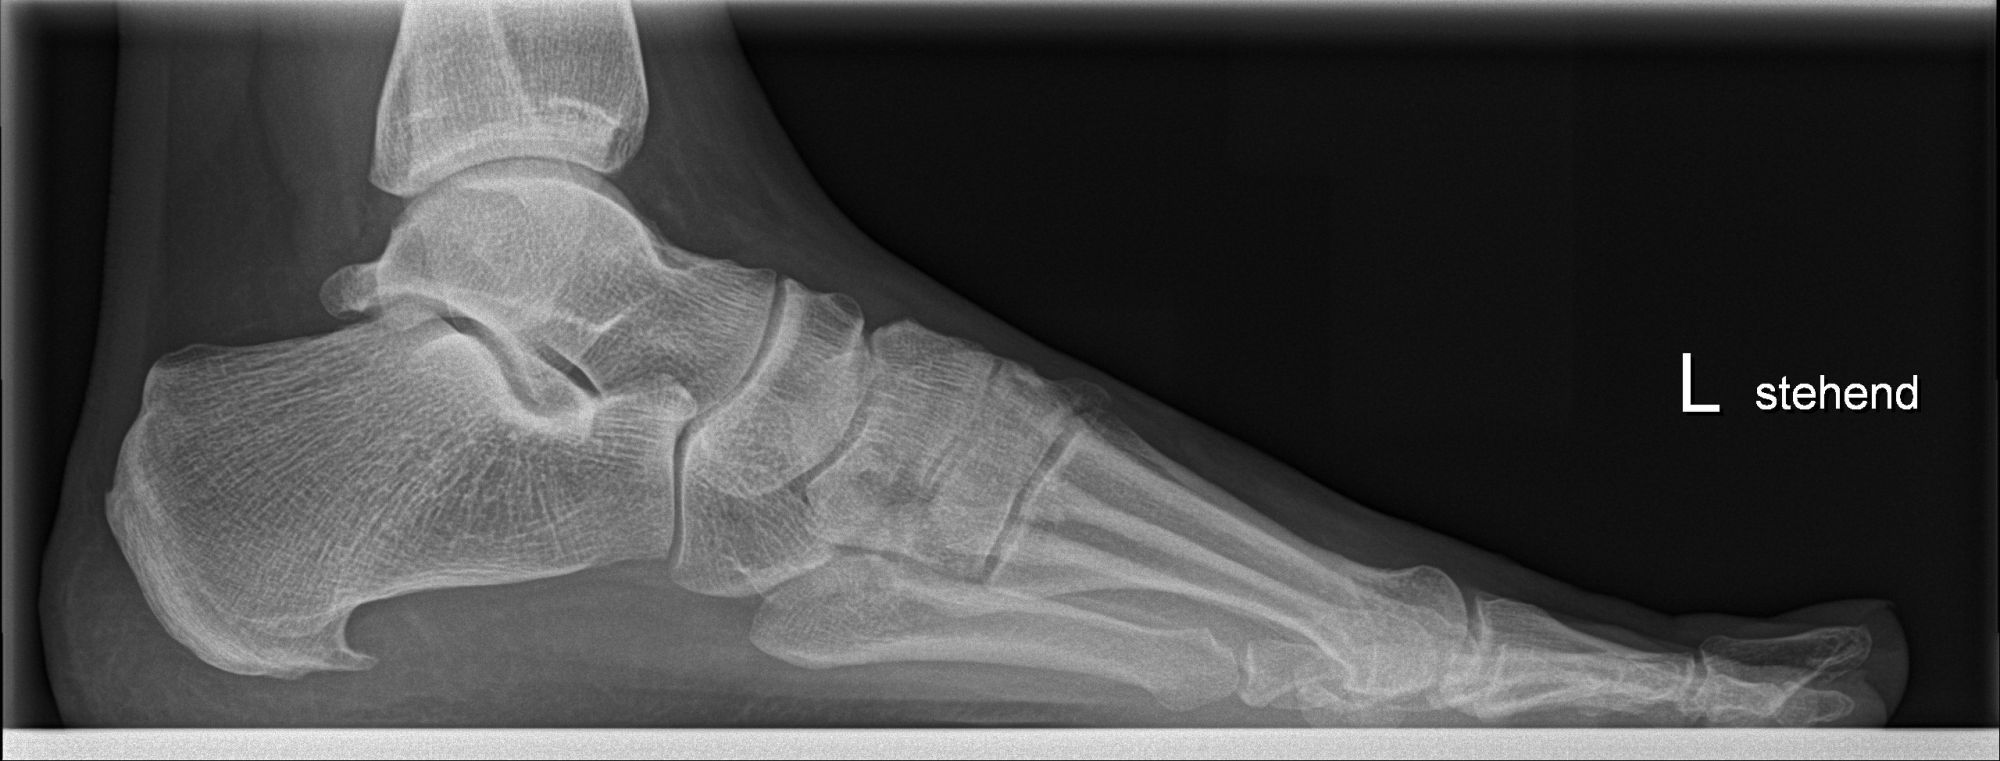

Abbildung 1: Plantarer und dorsaler Sporn im Röntgenbild und im MRT

Abb. 1a und Abb. 1b: großer dorsaler Fersensporn und ein minimaler plantarer Sporn, Patient, 50 Jahre.

Abb. 1c: Bild eines isolierten großen plantaren Fersensporns. Patientin, 32 Jahre.

Zum Lesen der Bildbeschreibung und zur Vollansicht bitte die Bilder anklicken. Bilder: Manfred Thomas.

Mit Hilfe von  Röntgenaufnahmen können knöcherne Abnormalitäten und Achsfehlstellungen ausgeschlossen werden. Folgen von Unfällen, wie zum Beispiel fehlverheilte Fersenbeinfrakturen oder überstehende Schrauben oder Platten nach osteosynthetischen Verfahren am Fersenbein können als Ursachen für plantare Beschwerden an der Ferse ausgeschlossen werden.

Konventionelles Röntgen (Fersenbein seitlich und tangential)

Arthrose der Fußwurzelgelenke, osteophytäre Ausziehung, plantarer oder dorsaler Fersensporn, Auffälligkeiten nach Unfällen oder Operationen (Fehlstellung, fehlpositioniertes Osteosynthesematerial, Fremdkörper), Veränderungen der Knochenstruktur (Ermüdungsfraktur, Osteoporose, Tumoren, etc.)

Dorsaler Fersensporn: Dorsale Fersenschmerzen können auch durch einen echten dorsalen Fersensporn entstehen (siehe Abb. 1). Dieser entsteht als knöcherne Ausziehung durch Verkalkung der Achillessehne an ihrem Ansatz.